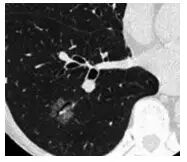

2. 马赛克灌注(Mosaic perfusion)

这是肺内通气灌注不一致的表现,主要是小支气管炎症导致肺内局部积气,像马赛克拼图一样